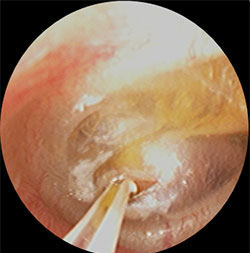

ただし、この滲出性中耳炎という病気は上記のような治療をしっかりおこなっても改善しないことが多々あります。2~3ヶ月このような治療おこなっても軽快していかない場合は、鼓膜を切開して小さい穴をあけ、滲出液を出すこともあります。鼓膜の穴は通常数日で塞がりますのでご心配なさらないで下さい。

また、このような状態を繰り返すようであれば鼓膜を切開したあとに小さいチューブを挿入して滲出液が溜まらないようにする方法もあります。もちろん、これらの処置をする場合は患者様(お子様の場合はお父様・お母様)とご相談の上、治療方針を決めていきます。当院では小児の鼓膜チューブ挿入も通常の外来で実施可能です。(場合により連携する総合病院へご紹介させていただきます。)

・上記の滲出性中耳炎の鼓膜に小さな切開をいれ、内部の液体を吸引し、鼓膜チューブを挿入